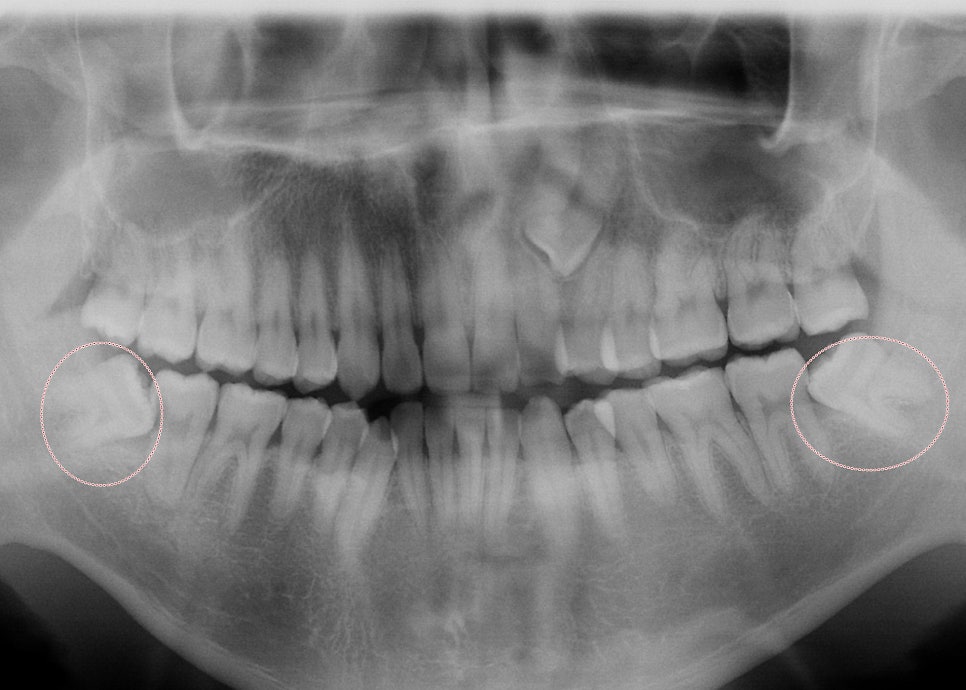

신논현역 치과 스마일 뷰에서 사랑니 발치를 위해 파노라마를 찍다 보면

정말 사랑니는 사람들의 사랑의 방법만큼이나 다양하다는 것을 알 수 있습니다.

사랑니는 케이스별로 발치 가능 여부가 결정되는데

저희 치과 구강악안면 외과 원장님께서는 3D CT로 정밀 진단을 한 후 대학병원에서나 가능한 사랑니를

안전하게 아주 쉽게 발치해 주신답니다.